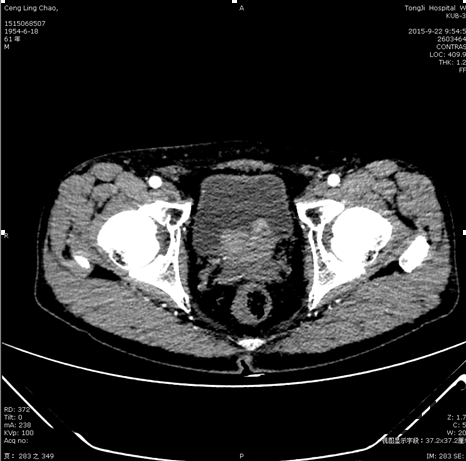

查体:T 36.3℃ P66 bpm Bp97 /51mmHg ,腹平软,无压痛及反跳痛,双肾区无叩痛,肠鸣音正常,双下肢无水肿。外生殖器无畸形。 辅助检查: 2015.9.14同济门诊B超示膀胱实质性占位,2015.9.17同济膀胱镜示膀胱多发占位性病变,尿道占位 CT:膀胱肿块,建议进一步检查;肝内低密度影,囊肿可能;左侧肾上腺结合部增粗,建议结合临床及进一步检查。胸椎、腰椎椎体多发结节影,建议结合临床及进一步检查。

诊断:膀胱肿瘤 处理:经尿道膀胱肿瘤电切术

随访:磁共振:膀胱肿瘤术后;膀胱三角区肿瘤性病变,侵犯前列腺、精囊可能; 双侧盆壁及双侧腹股沟淋巴结增多、增大。 病检结果示高级别尿路上皮癌前列腺来源可能性大。建议行进一步检查。 随访磁共振:膀胱肿瘤术后;膀胱三角区肿瘤性病变,侵犯前列腺、精囊可能; 双侧盆壁及双侧腹股沟淋巴结增多、增大。